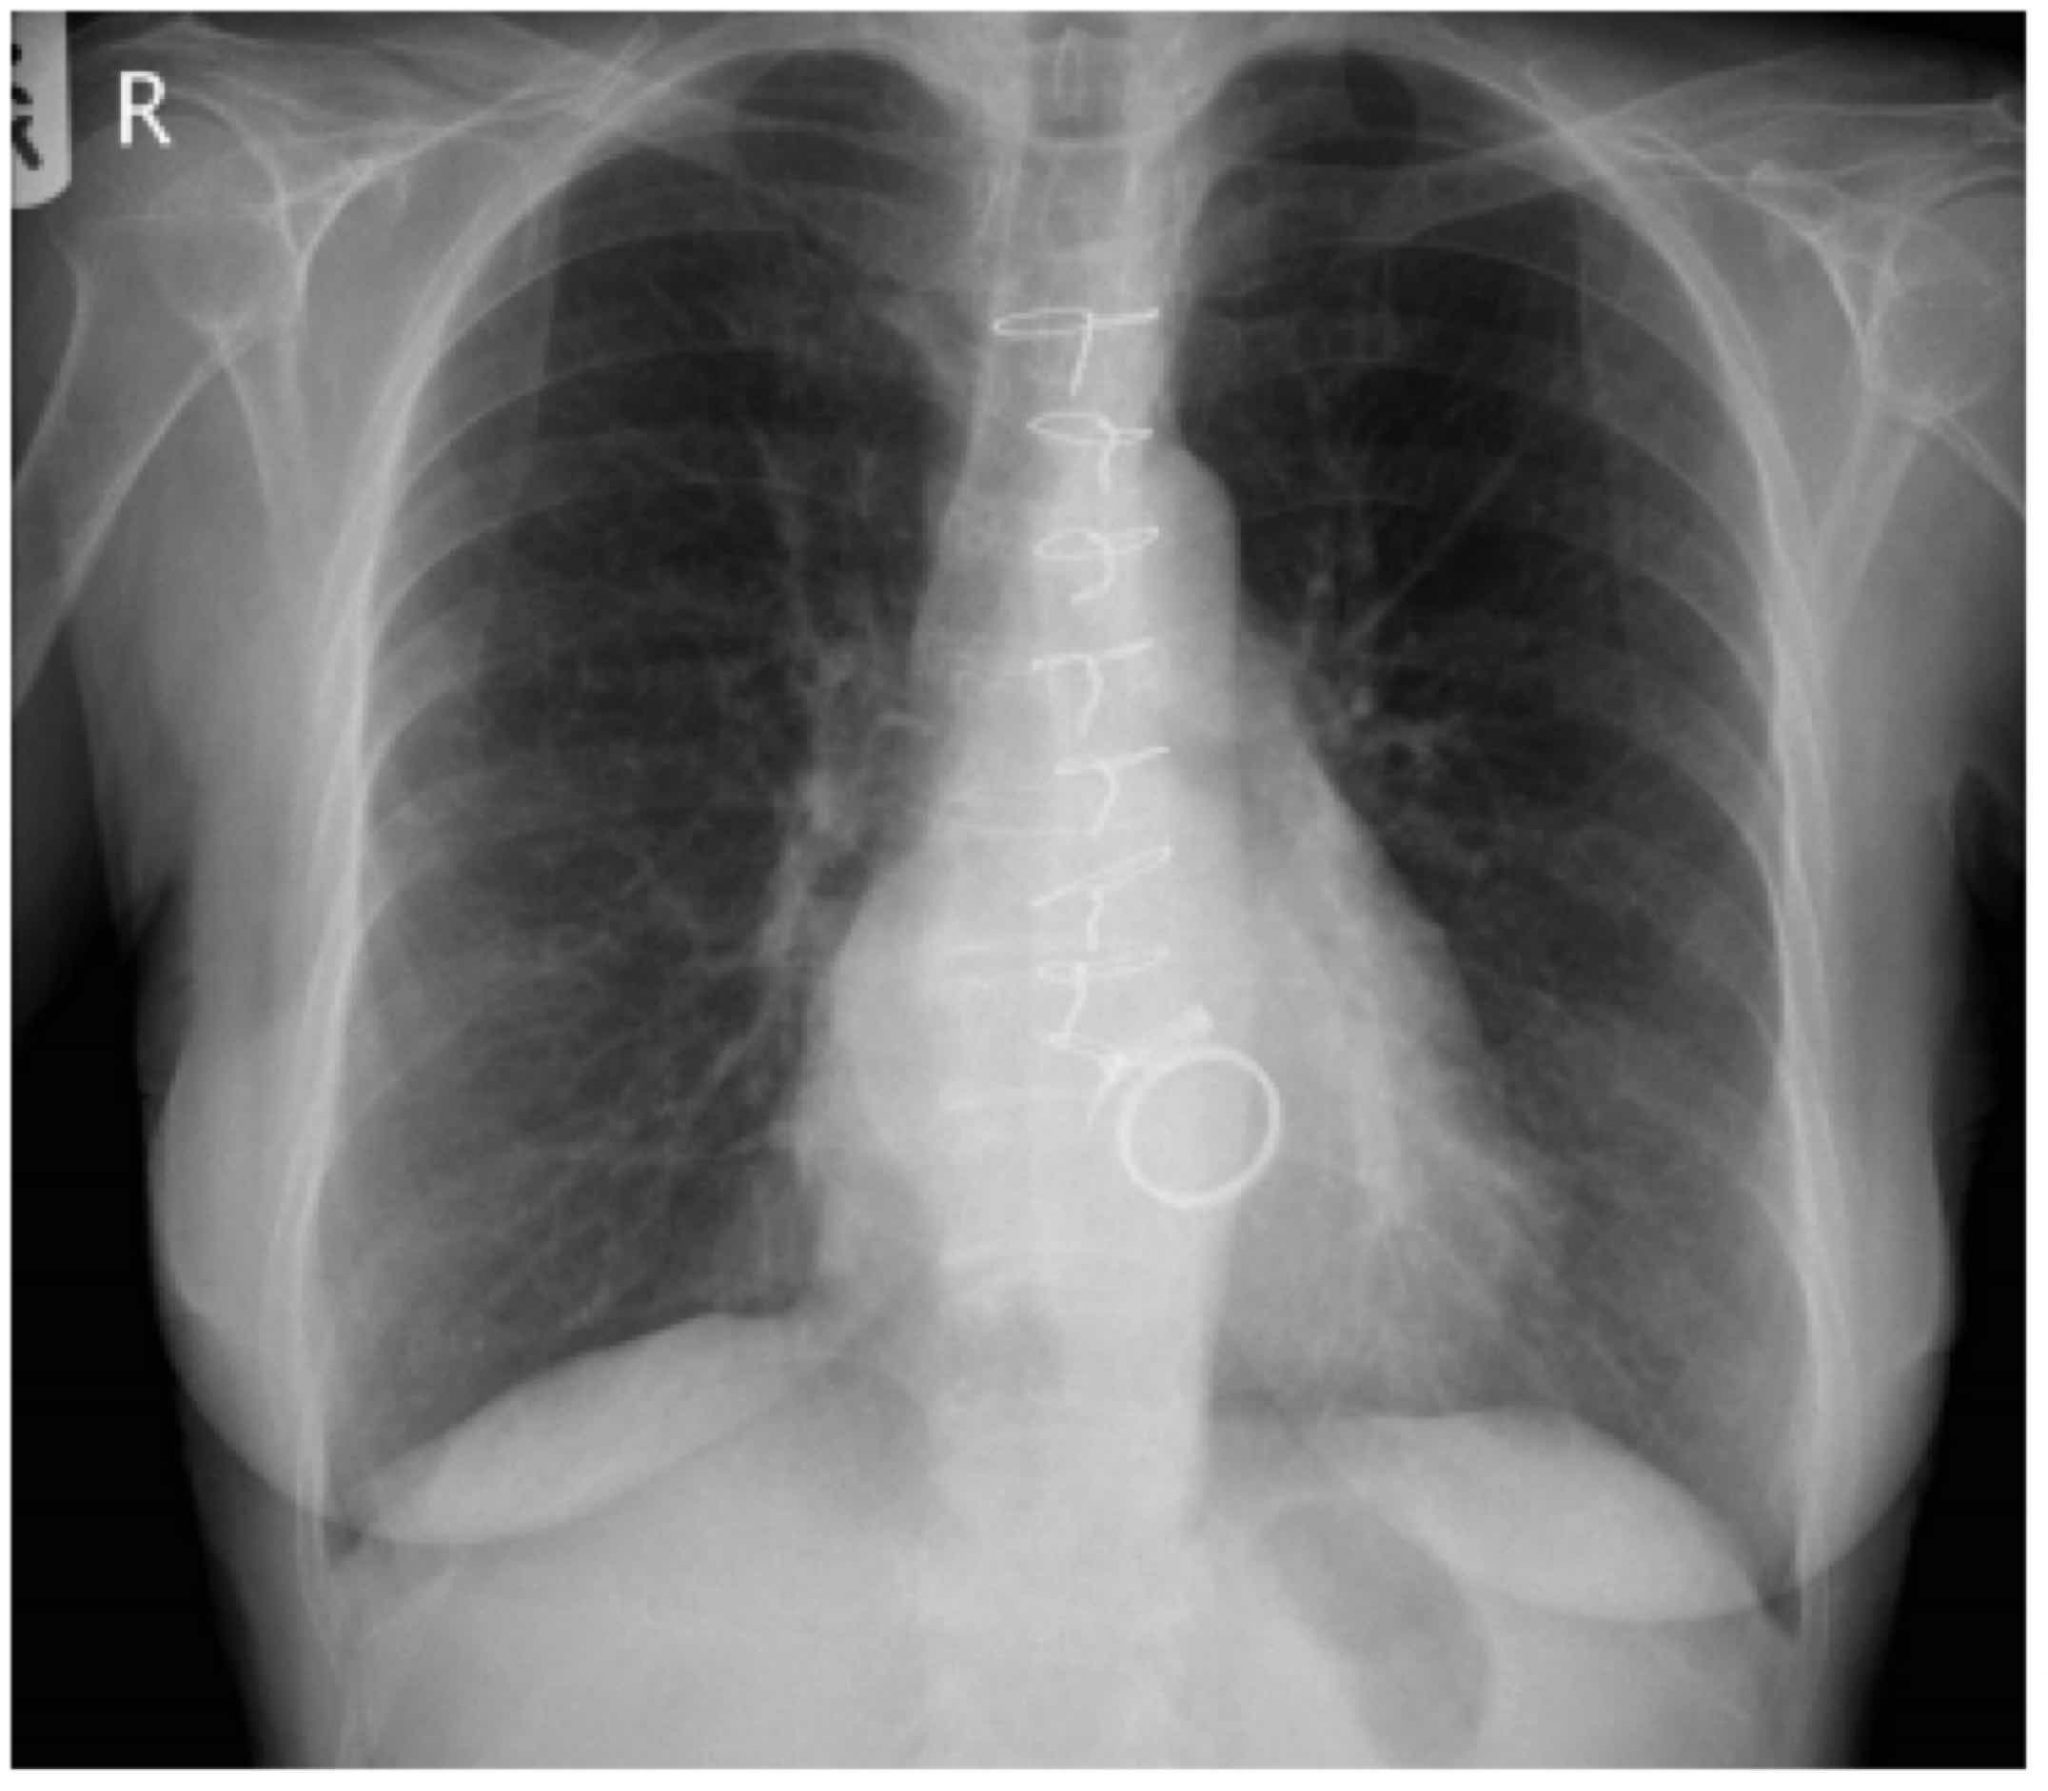

Chest xray showing clear lung fields. Download Scientific Diagram Chest X Ray Clear But Still Breathless There are no visible nodules, tumors or masses. They can also show ongoing lung conditions, such. It might feel like your chest is tight, you’re gasping for air or you’re working harder to. Your heart and lungs are involved in transporting oxygen to your tissues and removing carbon dioxide, and problems with either of. Shortness of breath, or feeling breathless,. Chest X Ray Clear But Still Breathless.